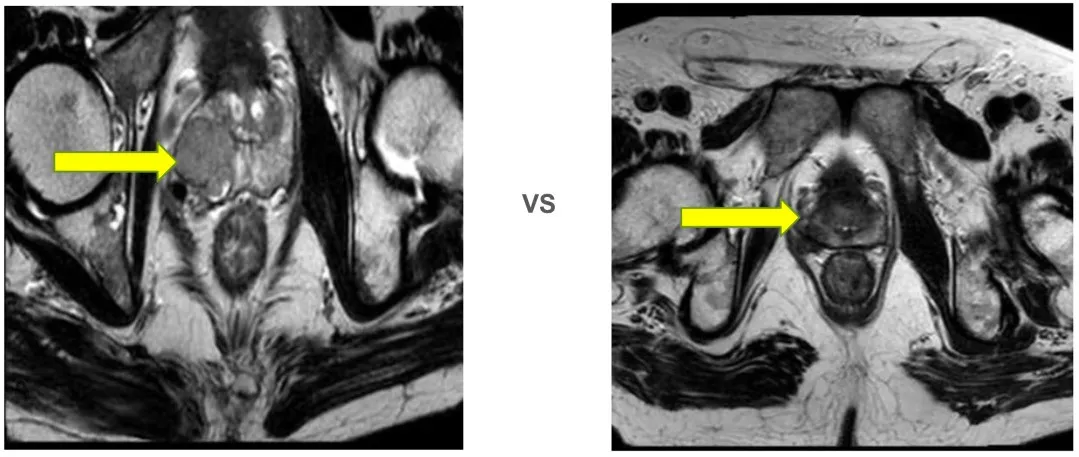

2025年9月12日 前列腺平扫+弥散(DWI)

(2024-11-28 vs 2025-9-12)

前列腺大小约为3.4cmx3.3cmx3.0cm,形态异常,右侧包膜欠光整,右侧周围带见结节状异常信号灶,T2WI低信号,T1WI低信号,DWI信号不高,边界欠清,长径约为0.9cm,左侧周围带信号不均匀减低,中央带及移行带信号不均。双侧精囊腺对称,充盈尚可。膀胱充盈可,其内未见异常信号灶。直肠因围脂肪间隙未见异常。扫描野内未见明显肿大淋巴结,扫描野内右侧股骨头及髋臼内见斑片状异常信号灶。

1. 结合病史,考虑前列腺右侧周围带肿瘤治疗后改变。

2. 右侧股骨头及髋臼异常信号灶,考虑退行性变可能。

前述改变与前片(2025-06)比较未见明显变化,建议隔期复查。